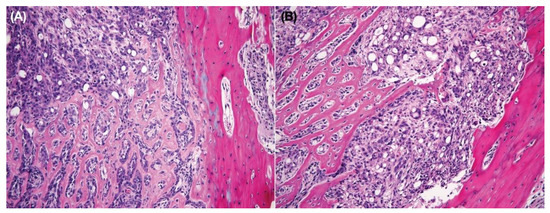

3.8. Intratibial Injection and JNK Inhibitor (SP600125) Treatment